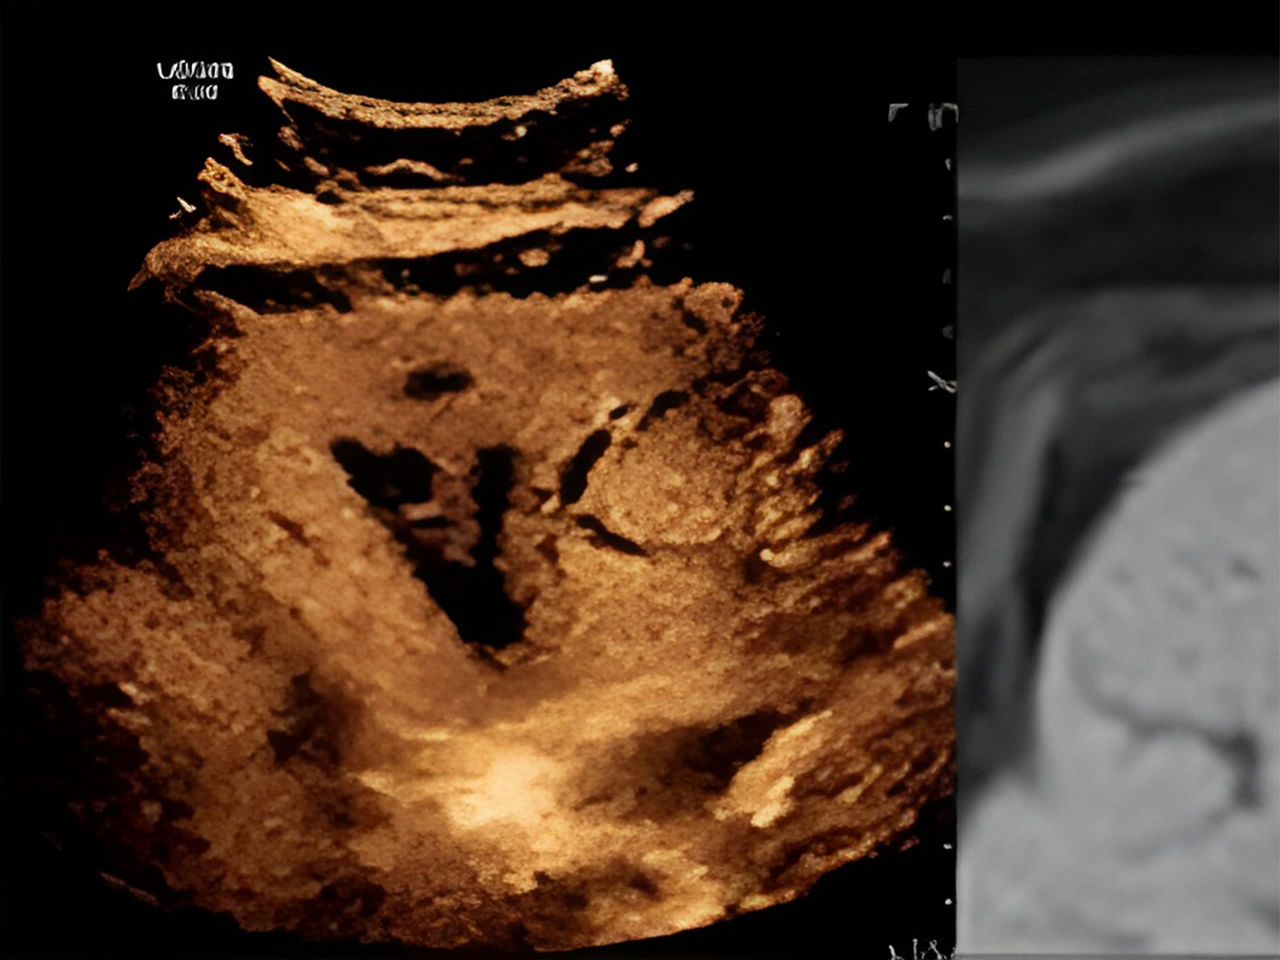

• B-Flow, Elastography, Multi-modality Query Retrieve

• 3D volume technologies, workflow concepts, volume manipulation and data optimization

• Describe and adjust parameters to acquire and display 3D and 4D volume datasets for maximum clinical utility.

• Manipulate volume datasets, (A, B & C planes in the X, Y and Z axis) for clinical correlation to specific clinical indications (i.e. nuchal translucency and post stent implantation procedures).